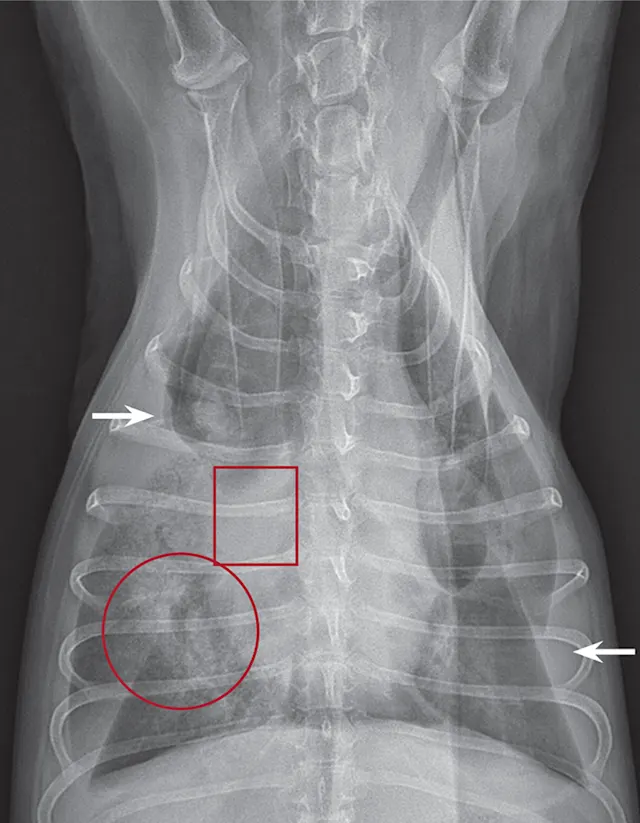

Thoracic radiographs (Figures 2–3) usually show pleural effusion and an opacified lung lobe. In acute cases, there may be an alveolar pattern in the affected lung lobe. A vesicular pattern (small, scattered gas bubbles) in the affected lung lobe; mediastinal shift; axial rotation of the carina; abnormal orientation of the bronchi in the affected lung lobe; and a curved, dorsally displaced trachea are common radiographic findings.2,5

Computed tomography (CT), thoracic ultrasound, and bronchoscopy may be helpful when thoracic radiographs are not diagnostic. CT images (Figure 4) show abruptly ending lobar bronchus of the affected lobe and noncontrast enhancing lung lobe enlargement in addition to pleural effusion and vesicular emphysema.5,6 The torsed lung appears rounded, hypoechoic, and surrounded by pleural effusion on ultrasonography.5 Definitive diagnosis is made by direct inspection at surgery or necropsy.

Figure 2

Ventrodorsal thoracic radiograph of a dog with right middle LLT. There is a vesicular gas pattern and alveolar pattern throughout the right middle lung lobe (circle), and the right middle lobar bronchus abruptly truncates near the hilus (rectangle). There is a moderate volume of pleural effusion evenly distributed within the pleural space, with moderate retraction of all lung lobes away from the thoracic wall (arrows).